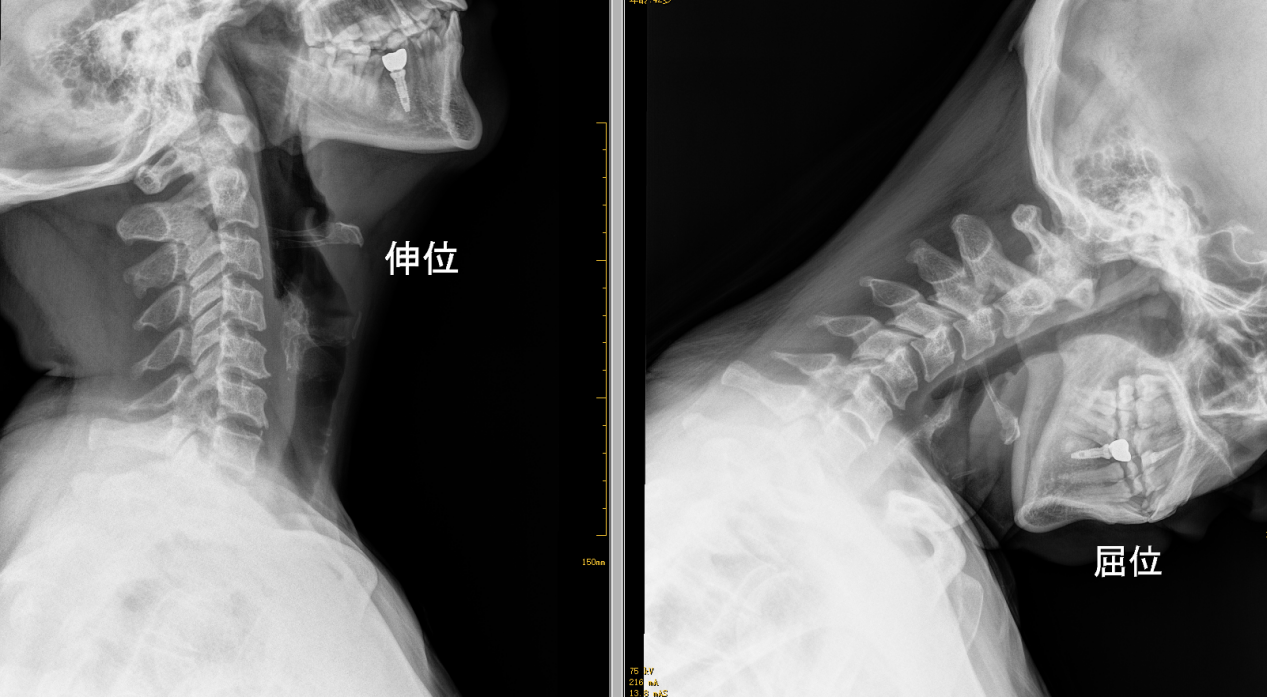

X线检查-动力位片